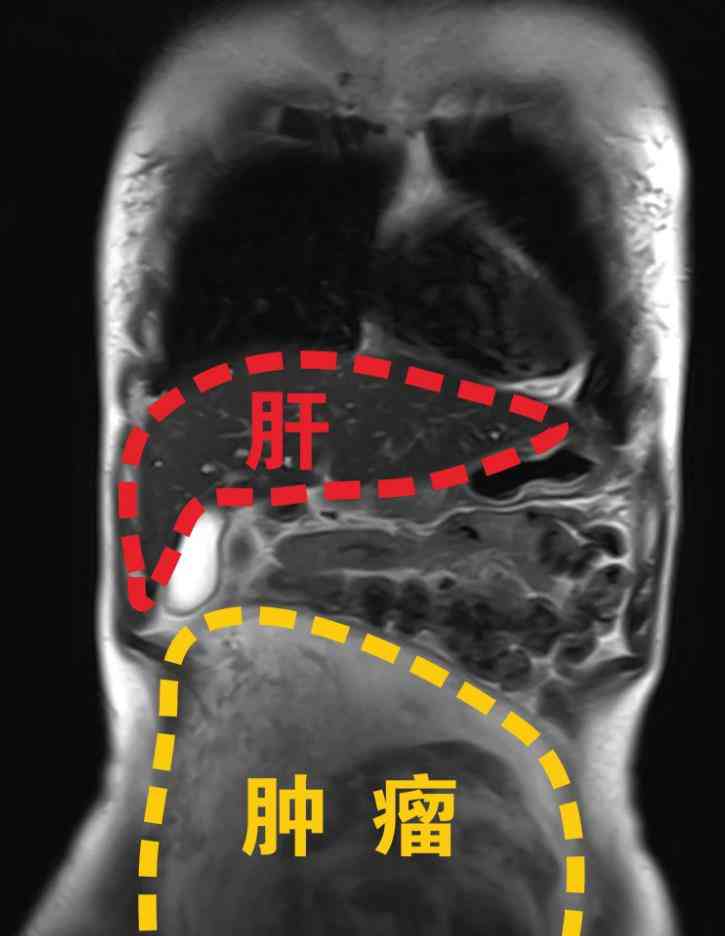

B超检查结果令人揪心:子宫上4cm的肌瘤、卵巢上5cm的囊肿,还有一个巨大包块从盆腔延伸至腹腔,上界抵达脐上120mm, 左右界达侧腹部,几乎占据了整个腹腔空间!P大姐随即被收入院,妇科团队考虑到包块巨大、性质与来源不明,决定进行剖腹探查术,并同步开展快速冰冻切片病理检查。

快速冰冻切片病理检查结果显示,这是一个来源于左侧阔韧带的巨型梭形细胞肿瘤,考虑平滑肌瘤,重达2250g,大小有22.5*20*7cm,犹如一块小型平板电脑!